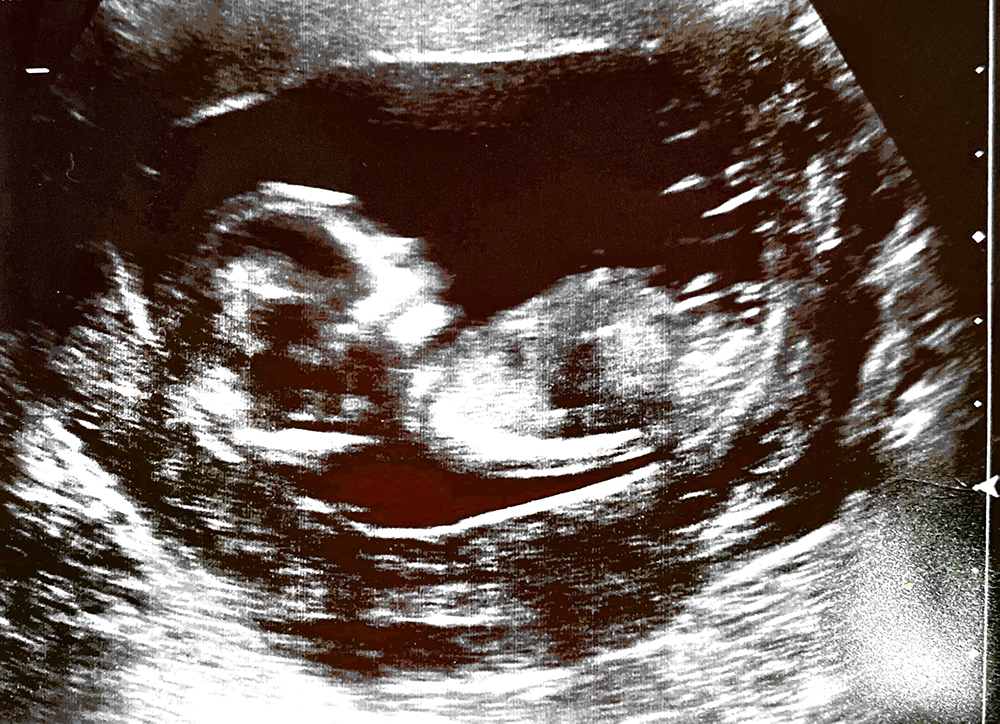

These are probably low quality as our hospital don't give digital copies so I had to scan these in, and four kids in I still never know what I'm looking for on these scans...but can anyone see a nub or have any boy /girl guesses on my 13 + 5 scans?

Attachment 42268Attachment 42269